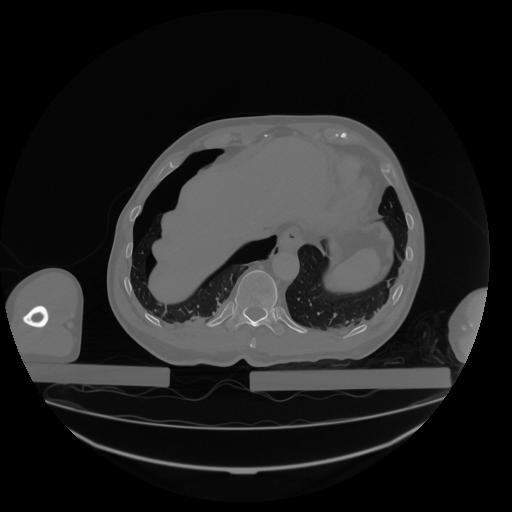

34 CUERPO,CE,Vol,1.0,CUERPO,,